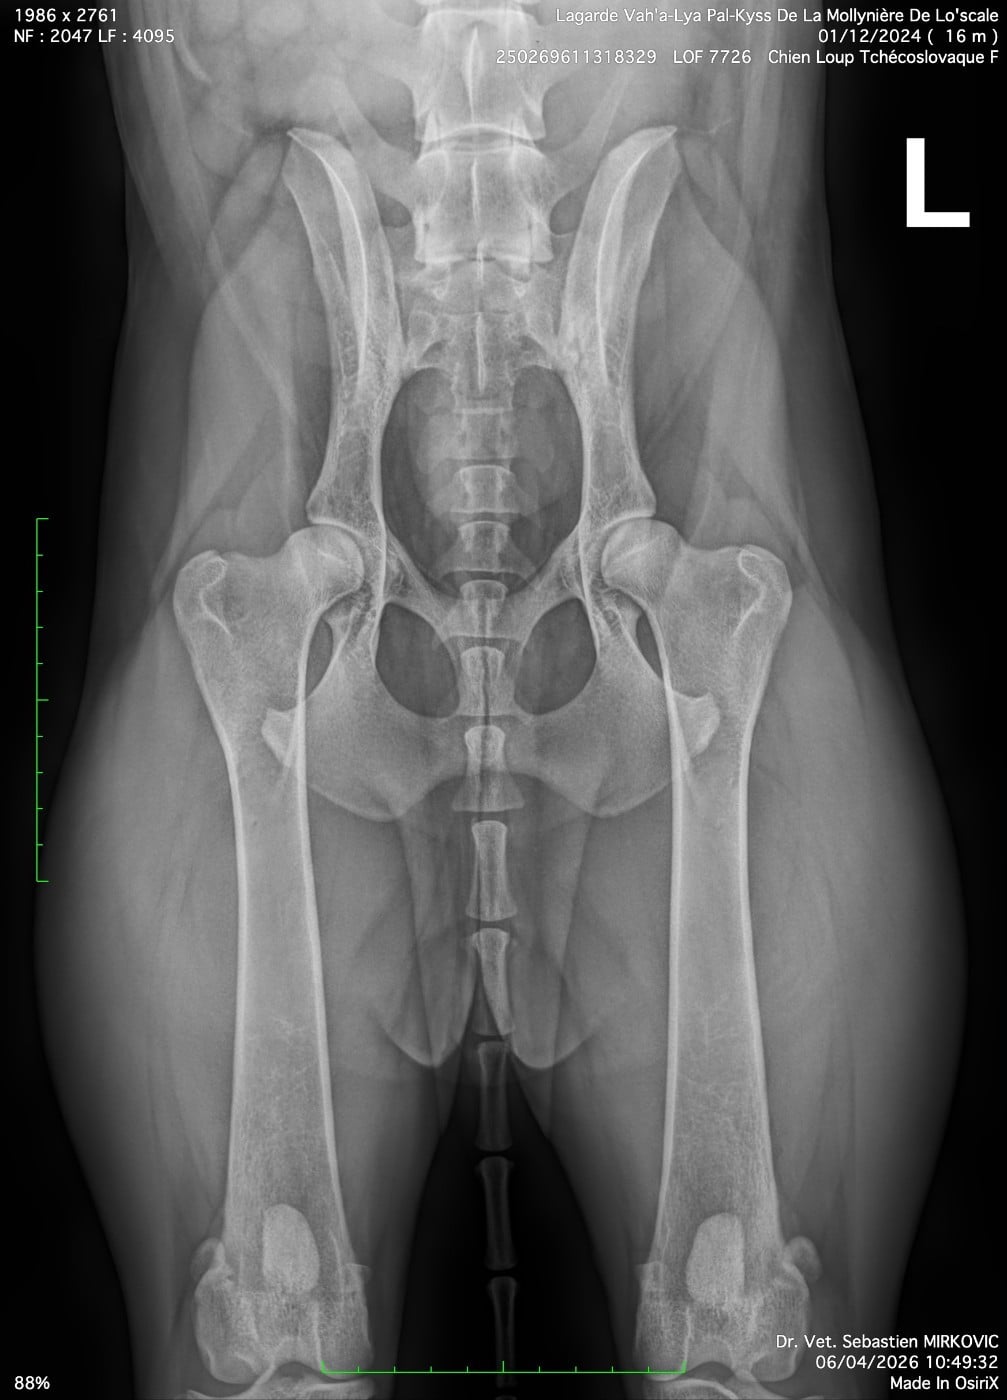

Sensibilité Médicamenteuse - Saine (N/N) Porteuse Poils Longs - NonMyélopathie Dégénérative - Saine (N/N)Nanisme Hypophysaire - Saine (N/N)Dysplasie Hanches - B - Sensiblement normalDysplasie Coudes - ED-0 - Indemne